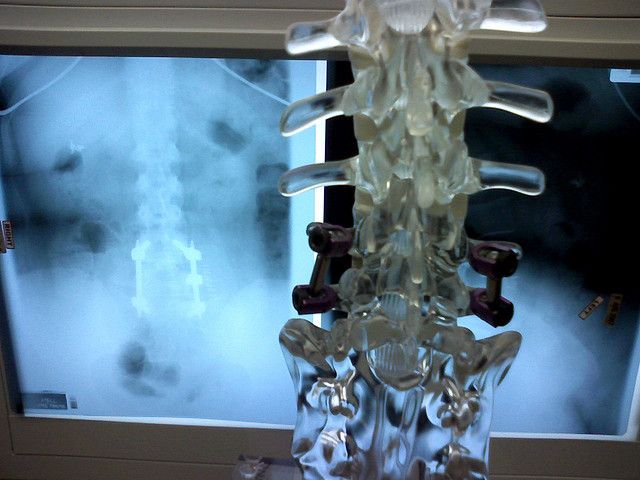

Perhaps the most amazing so far, however, involves a newly-launched medical technology which allows chronic pain patients to use their iPod Touch to interrupt the pain signals travelling up their spinal cord on their way to the brain.

Called the Invisible Trial System because it can be worn under clothing, the technology uses Bluetooth to control a device which delivers low levels of electrical energy to nerve fibres, thereby masking or interrupting pain signals.

While the iPod touch is the primary device used by the patient to control the therapy, an iPad mini is also used by the patents’ physician to set the programming parameters. This is the medical industry’s first neuromodulation trial system to use both Apple and Bluetooth technology.